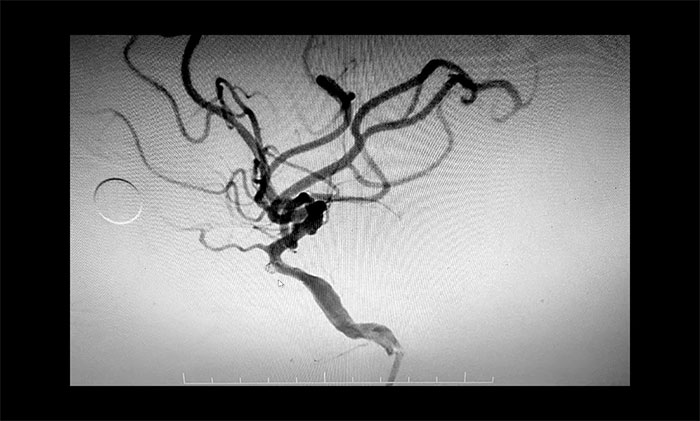

在明確告知患者家屬手術(shù)風(fēng)險(xiǎn),并取得同意后,于耀宇主任團(tuán)隊(duì)在麻醉科和介入手術(shù)室緊密配合下,為患者開(kāi)展經(jīng)導(dǎo)管顱內(nèi)動(dòng)脈瘤彈簧圈栓塞術(shù)。手術(shù)過(guò)程順利,術(shù)后患者恢復(fù)情況良好。

▲ 動(dòng)脈瘤順利栓塞,不顯影